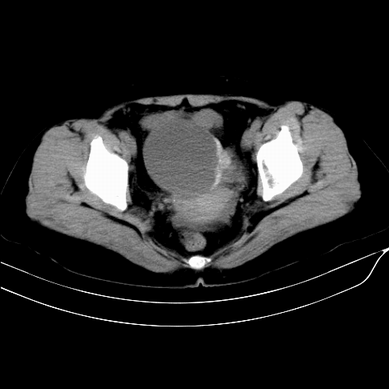

以下是引用zsl6918在2008-6-5 13:49:00的发言:[br]右侧附件区囊性占位,边可见钙化改变,底可见实性结节,考虑囊腺瘤可能性大.

以下是引用zjzjr在2008-6-5 17:29:00的发言:[br]可见壁结节,支持囊腺瘤可能性大.